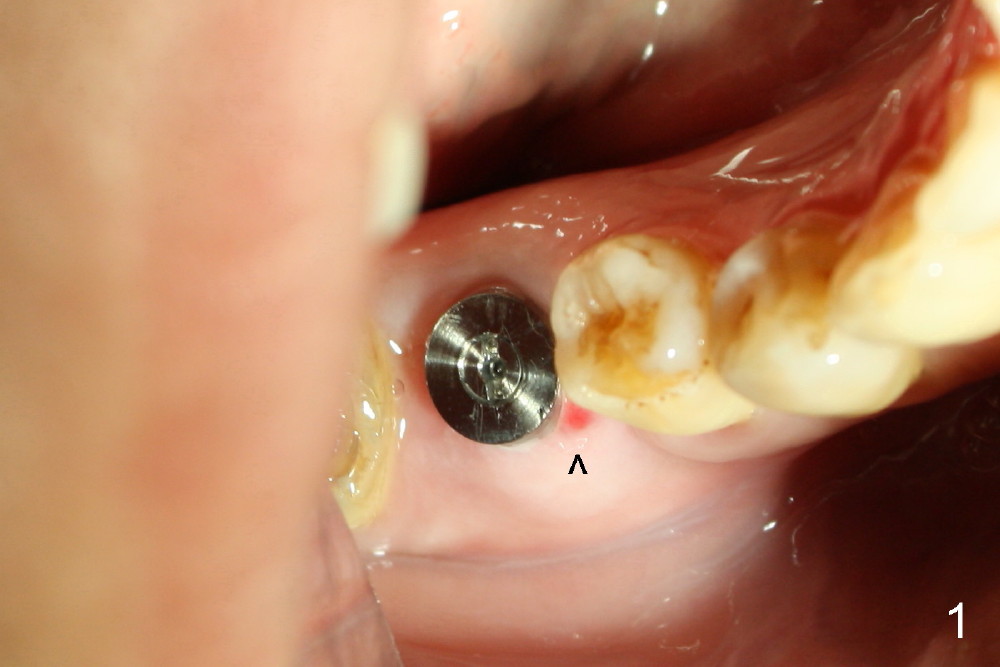

The tooth #30 was extracted in other office 1 month ago. The socket appears to heal normally. A tissue-level implant is placed as planned and smoothly. No antibiotic is prescribed pre- or post-op. The patient reports mild pain 1 week postop. There is a sign of infection. Amoxicillin is prescribed. One week later, the symptom improves, but the infection signs are present (Fig.1). The implant has mobility and is removed (Fig.2). The osteotomy is thoroughly debrided, followed by copious irrigation with normal saline and Clindamycin soaking. Irradiated cancellous bone graft (.5 mg) is placed (Fig.3,4). The wound is covered by collagen plug (Fig.5) and sutured with Chromic gut (Fig.6). Amoxicilin is prescribed postop. One week follow up reveals normal wound healing (Fig.7 (buccal view), 8 (lingual)).